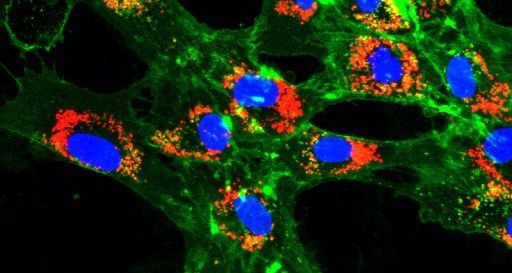

A dnes už vím, že některé vlastnosti nádoru mohou léčebnou účinnost nanočástic ovlivnit. Třeba nadměrný extracelulární matrix, tedy mimobuněčná hmota, která se nachází mezi buňkami tkání. V místě nádoru může tedy fungovat jako fyzická bariéra, která brání pronikání léčiva. Chci studovat, jak nanočástice s různými složkami nádorového mikroprostředí interagují. Projekt, na kterém teď pracuji, by měl identifikovat vlastnosti nanočástic, které umožní lepší průnik, a tím pádem účinnější distribuci léčiva. Věnuji se léčbě zaměřené přímo na extracelulární matrix a jeho hlavní producenty – fibroblasty.

Různé typy nanočástic mají různé mechanismy. Na University of Melbourne pracuji se dvěma typy, ten první se nazývá glykogenové, to jsou přírodní nanočástice, které jsou poměrně biokompatibilní. To znamená, že obvykle nejsou pro buňky toxické. S týmem Franka Carusa zaměřujeme na tzv. metal-phenolic network nanoparticles (volně přeloženo jako metal-fenolové síťové nanočástice). Oba typy můžou být použity jako nosiče chemoterapeutického léčiva. Dnes už je možné jimi distribuovat také různé typy nukleových kyselin a využít je tak pro RNA terapie. Po zapouzdření molekul těchto látek se nanočástice použijí k transportu přímo na místo nádoru. To provádíme změnou povrchových vlastností, aby nanočástice měly k určitým buňkám větší přitažlivost než k jiným. Případně jde také k nanočásticím připojit určité protilátky, které samy rozpoznají určitý typ buněk. Pokud to shrnu – nanočástice jsou malé nosiče účinných látek, které umí dopravit na potřebné místo, tedy do nádoru.

Nejjednodušeji se nanočástice pozorují pomocí fluorescenčního značení. Pokud zbarvíme jejich povrch nebo vnitřek, můžeme sledovat jejich pohyb uvnitř buněk nebo uvnitř tkání laboratorních myší.